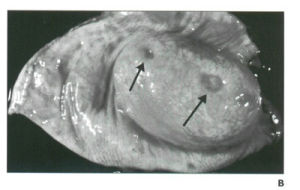

磁共振成像檢查:大體標本可見黏膜肉芽腫和線裂狀潰瘍,典型的成“鵝卵石”樣。

3、肉眼特點:潰瘍,狹窄,鵝卵石樣及假息肉等。